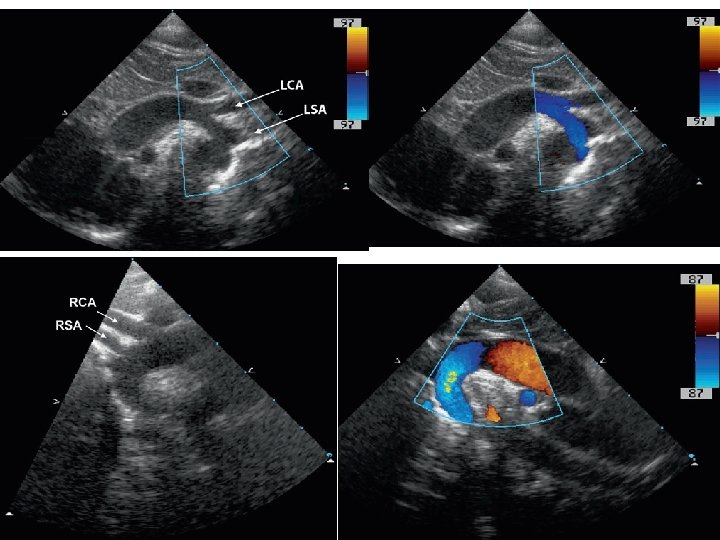

Cervical aortic arch

Cervical arch-different types